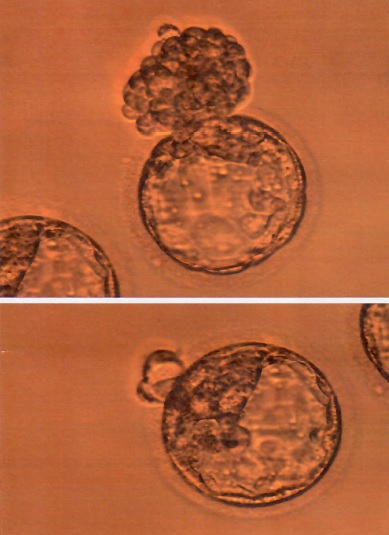

因為王太太有2次不如預期的懷孕經驗,所以在計劃生第3胎之前,特別到本院接受試管療程,前後共進行取卵手術2次,共取得30多顆卵子,但在與精子結合後,只有9顆胚胎存活下來,且其中只有3顆胚胎是正常基因。「為防範植入的胚胎帶有「裘馨症」的基因,我建議她接受「胚胎著床前基因診斷(PGD)」,這項技術能篩選出帶有異常致病基因的胚胎,才得以挑出王太太最好的2顆正常胚胎做植入,也順利生下健康的龍鳳胎」;王太太還有1顆正常基因胚胎冷凍存放在醫院,未來她想再生的話,也會是健康的孩子!

李茂盛院長強調,「胚胎著床前基因診斷(PGD)」是在胚胎發育的第3天的八細胞期取出單一胚葉細胞或從第5天的囊胚取出數個滋養層細胞來進行染色體數量及基因型或缺陷基因的分析,藉此找出染色體數量正常與不帶有家族性遺傳疾病的胚胎,避免生下帶有基因缺陷的胎兒,也能增加胚胎的著床率及懷孕率。意即,裘馨症、小腦萎縮症、法布瑞氏症、地中海型貧血、僵直性脊椎炎、多囊性腎病變、染色體轉位異常…等多種罕見疾病或是家族性基因遺傳疾病就得以被阻斷在代間遺傳,可為遺傳性疾病的家庭帶來生命新契機,想懷孕生子的帶因父母再也不用擔心受怕了。